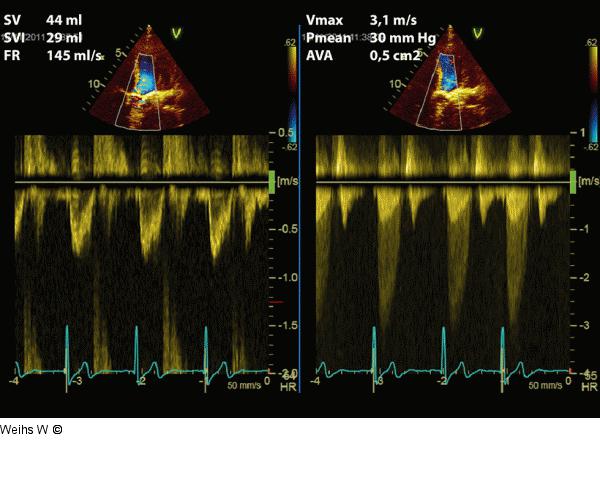

Abbildung 2: Aortenstenose Die Quantifizierung der Aortenstenose anhand der Dopplerparameter ergibt eine paradoxe Low-flow-low-gradient-Aortenstenose. |

Die Quantifizierung der Aortenstenose anhand der Dopplerparameter ergibt eine paradoxe Low-flow-low-gradient-Aortenstenose. |